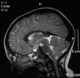

Midline dermoid

Dermoid sinus is a thought to be a genetic skin condition in dogs. It is also known as pilonidal sinus. [Source: Wikipedia ]